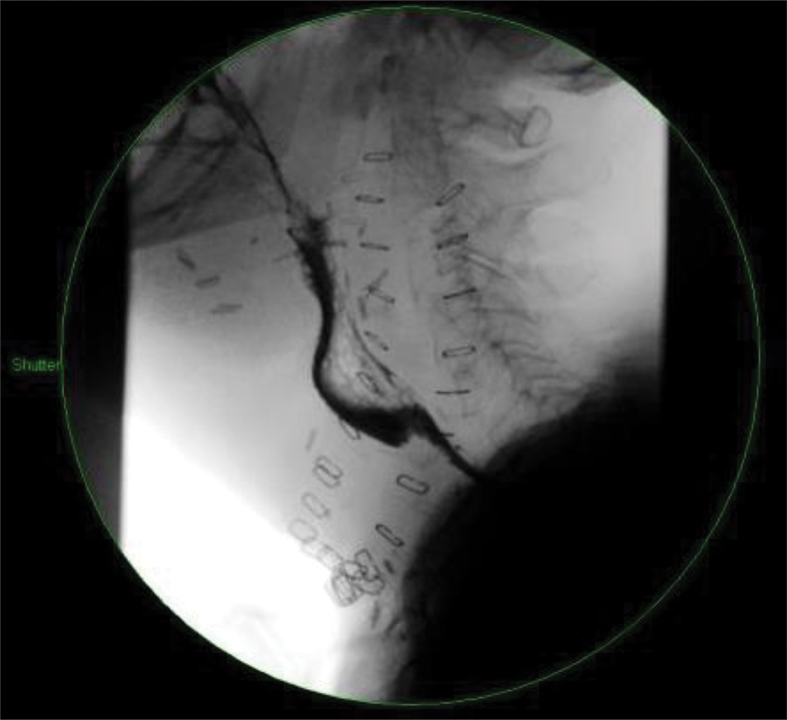

On postoperative day 8, the patient was noted to have a pus-like discharge from a previous drain site on the right side of the neck. A contrast swallow study showed that there was no leak or obstruction (Fig 1). Swabs were sent, which cultured extended-spectrum beta-lactamase Escherichia coli, and the patient was started on meropenem.

Figure 1.

Contrast swallow study

Over the following 2 weeks, the right neck drain site continued to intermittently discharge a creamy pus-like fluid. Further swabs did not culture any bacteria. Contrast swallow studies were repeated on postoperative days 13 and 16 but, again, they showed no leak or obstruction. The patient remained clinically well and was entirely asymptomatic for what was presumed to be a postoperative collection of pus in the neck.